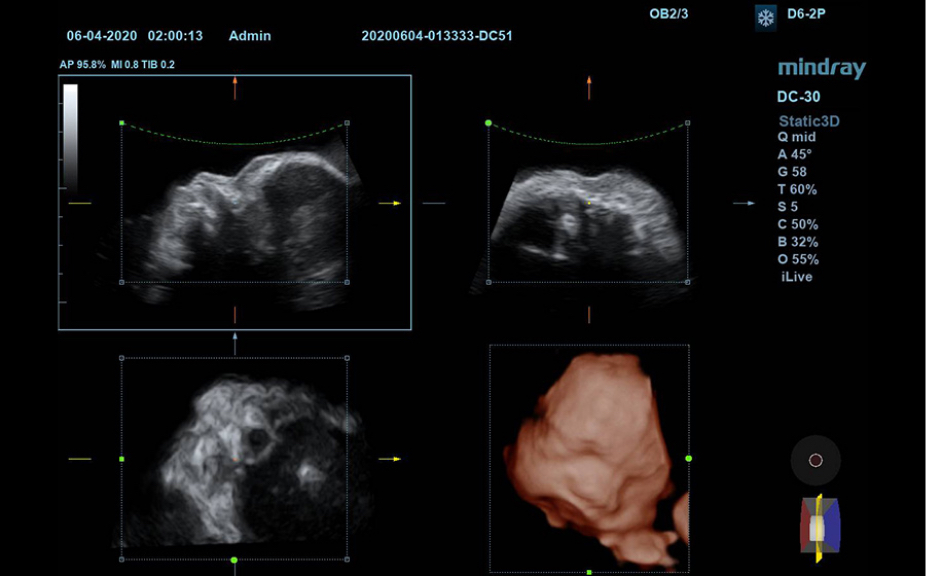

Normale anatomische illustraties met inbegrip van schematische beelden en ultrasoundbeelden.

Zijdelingse weergave van een standaard ultrasonogram dat visuele aanwijzingen geeft over de relevante gebieden.

Standaard ultrasoundbeelden

3

Vergelijking realtimescan ter referentie.